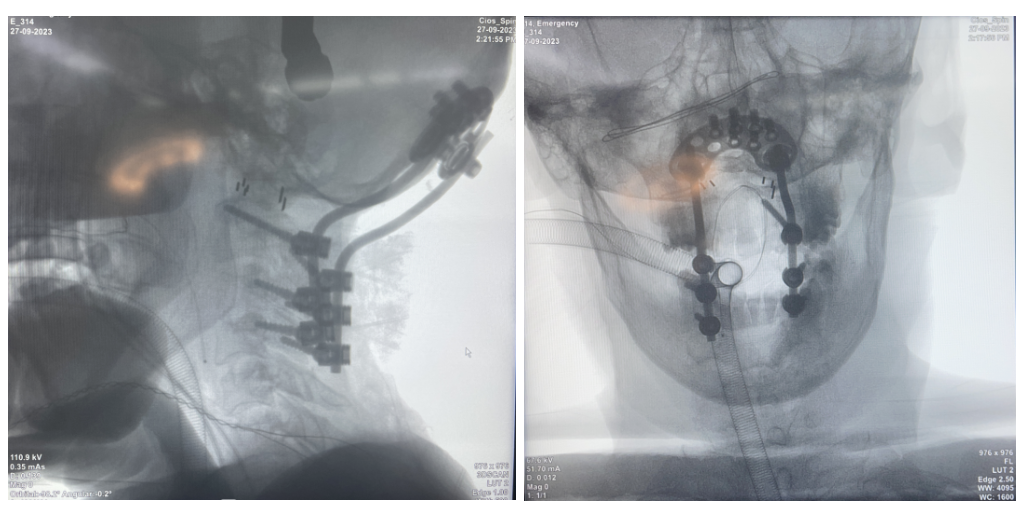

病例(li)一

簡介:

友商枕頸融合術后1年2個(ge)月拔釘,使用我(wo)司枕頸產品翻(fan)修。

患(huan)者枕骨區域(yu)骨質薄,使用(yong)φ4.5×5mm螺釘(ding)6枚,術后隨訪效果良好。